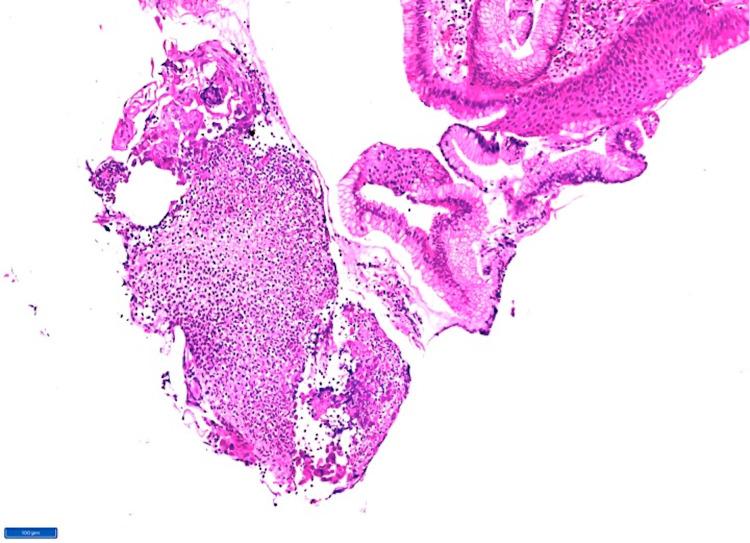

Herpes simplex infection remains the third most common cause of esophagitis following gastric reflux disease and candida infection. This disease usually occurs in immunocompromised individuals; however, it has been frequently reported in healthy individuals. We present a case of a 39-year-old man who presented to the ER with symptoms unusual of herpes esophagitis. He was presumed to be immunocompromised due to uncontrolled diabetes mellitus and chronic alcohol use. Endoscopy revealed features in favor of candidiasis; however, histopathology displayed characteristic features of herpes infection. Herpes esophagitis should thus be suspected in immunocompromised patients with an independent underlying pathology and treated early with antiviral agents like acyclovir to prevent impending complications.

单纯疱疹感染仍是继胃反流病和念珠菌感染之后食管炎的第三大常见病因。这种疾病通常发生在免疫功能低下的个体中;然而,在健康个体中也经常有病例报道。我们报告一例39岁男性患者,他因出现单纯疱疹性食管炎不常见的症状而就诊于急诊室。由于糖尿病控制不佳和长期酗酒,推测他免疫功能低下。内镜检查显示有念珠菌病的特征;然而,组织病理学表现出疱疹感染的特征性表现。因此,对于有独立基础疾病的免疫功能低下患者,应怀疑患有单纯疱疹性食管炎,并应尽早使用阿昔洛韦等抗病毒药物进行治疗,以预防即将出现的并发症。